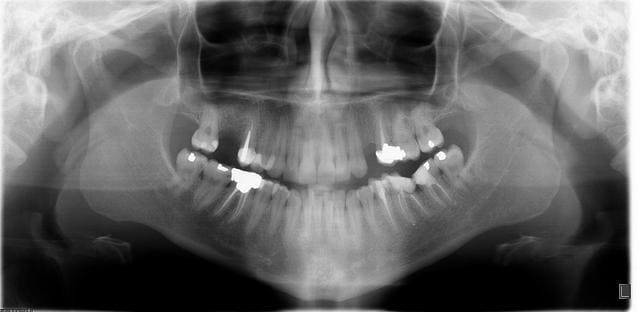

Par exemple, pour cette jeune patiente X, en normocclusion, et sans parafonctions, qui souhaite le remplacement de la 24.

Ou encore, danss le cas d'une hémisection radiculaire avec conservation de la racine distale sur 46, pour cette patiente Y. Pour moi, un taquet d'appui sur 45 pourrait être intéressant pour répartir les charges...

Patiente y btg3qg - Eugenol

Pour la patiente X: le taquet d'appui sur 23 peut sembler a priori une bonne idée, le problème, c'est que dans le temps ça ne va pas très bien se passer( risque de déscellement de l'aillette, de reprise de carie sous celle-ci et de contraintes trop importantes sur 25). Mieux vaut un implant ou un bridge classique si tu veux dormir sur tes deux oreilles.

Pour la patiente Y: les hémisection, amputations: très peu pour moi.

Tu auras tjs des pb de nettoyage, et en plus tu as un gros risque de fracture de la racine.

Donc, extrait la dent.

pour les hémisections, bien faites dans des bons cas, ça marche ; après, je suis pas sur que ton cas soit idéal pour ça vu la racine distale qui semble cariée jusqu'au niveau osseux, on retombe dans l'approximatif.

Pour moi il est étonnant de vouloir remplacer cette 24 et que fait on pour la 16?

Malgré ça si tu veux remplacer la 24 il me semblerai plus raisonnable de faire un bridge en extension 26-25-24. Et surtout dans ce cas là sans tacquet sur 23!!!

Pourquoi conserver la racine distale et pas la mésiale, elle semblent toutes les deux aussi mal en point! Si tu veux conserver malgré tout pour moi le cas se prête plus à élongation coronaire et prémolarisation. Mais je pense que la dent est à extraire en entier et puis c'est tout.